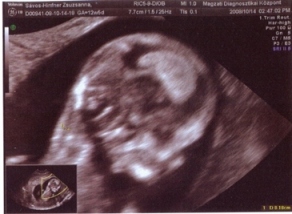

Hűűű a hétvége nagyon jó volt! a 4D-t lemondtam, igy kinyomtattam a fényképet a babóról, és beleragasztottam egy képeslapba, amire ráirtam, hogy